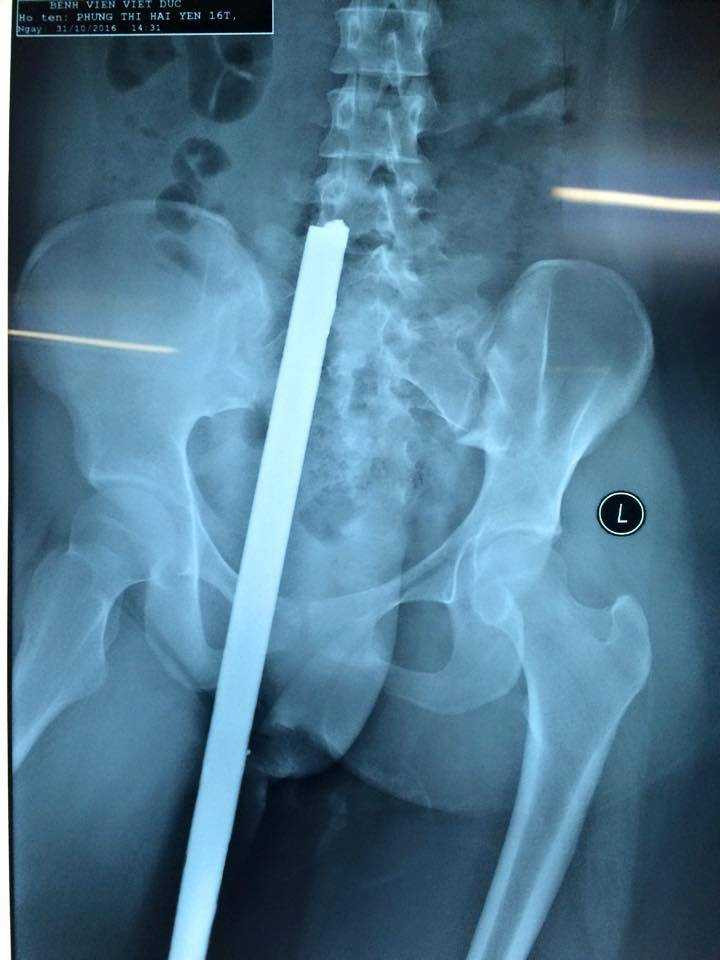

Theo Điều dưỡng Nguyễn Ngọc Thực, bệnh nhân nhập viện lúc 16h50 ngày 31/10, trong tình trạng thanh sắt vẫn cắm ở trong người. Kết quả chụp X-quang cho thấy, thanh sắt dài khoảng 40 cm đâm từ phía sau, dưới mông xuyên đến tận thắt lưng.

Kết quả chụp X-quang cho thấy, thanh sắt dài khoảng 40 cm đâm từ phía sau, dưới mông xuyên đến tận thắt lưng nạn nhân.

Bệnh nhân nhanh chóng được làm các xét nghiệm, chụp chiếu cần thiết, sau đó được chuyển thẳng tới phòng mổ. Sau ca phẫu thuật, các y bác sĩ đã rút được thanh sắt ra khỏi cơ thể nạn nhân.

May mắn, thanh sắt chỉ đâm vào phần mềm, không ảnh hưởng đến xương và thần kinh nên sau ca phẫu thuật, tối cùng ngày, sức khỏe bệnh nhân đã ổn định hơn và tiếp tục được theo dõi. “Dự kiến, bệnh nhân sẽ phải nằm viện 1 tuần”, Điều dưỡng Nguyễn Ngọc Thực cho hay.